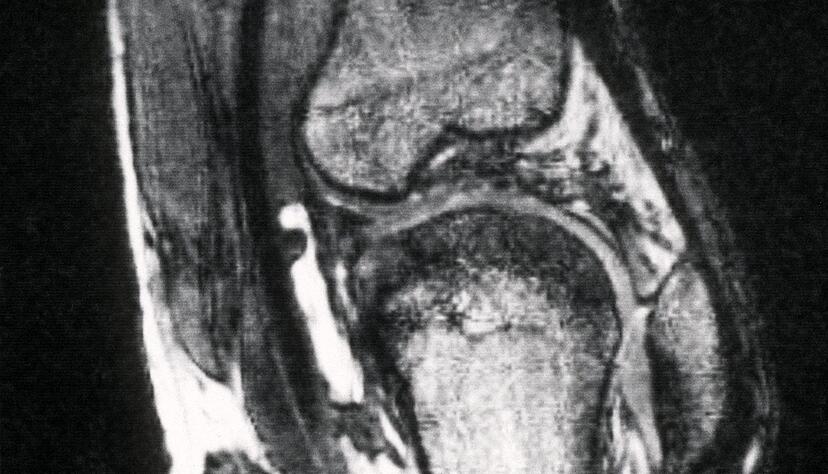

Spritzen bei Knie- und Hüftgelenksarthrose

Bei den Knie- und Hüftspritzen geht es um Injektionen mit Hyaluronsäure, die fehlende Gelenkflüssigkeit ausgleichen soll. Diese Spritzen kosten pro Behandlungszyklus zwischen etwa 220 und 300 Euro. Je nach verwendetem Präparat können aber auch 500 Euro und mehr fällig werden. Dabei überwiegen bei diesen Spritzen mögliche Schäden den Nutzen laut Medizinischem Dienst deutlich. Dies gehe aus zahlreichen Studien hervor, mit denen diese Injektionen seit über 50 Jahren bewertet würden, so der Medizinische Dienst.

Dass die Spritzen gefragt sind, liegt an der weiten Verbreitung der Arthrose und dem Fehlen einer heilenden Therapie. Schätzungsweise ist in Deutschland jede sechste Person zwischen 60 und 80 Jahren von einer Kniegelenks- und jede und jeder Zehnte von einer Hüftgelenksarthrose betroffen - bei Über-80-Jährigen deutlich mehr. Im Gegensatz zur Hyaluronsäure-Injektion werden mehrere Behandlungen, die die Schmerzen lindern und die Beweglichkeit verbessern sollen, von den Kassen übernommen - bis hin zu Gelenkersatz bei schwerer Arthrose.